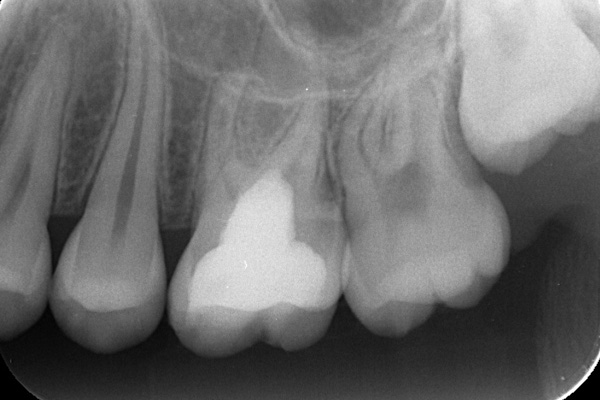

「歯に穴が空いて食事の時に痛む」という主訴でご来院されました。他院で治療を受けた箇所であり虫歯が非常に深く、通常であれば神経を全て抜く「抜髄(ばつずい)」が必要な状態でした。今回は若年者ということもあり将来的なことを鑑み神経の一部を温存する「部分的断髄法(VPT)」を提案しました。高い殺菌性と封鎖性、そして組織の再生を促す効果を持つMTAセメントを使用して神経を保護し、歯質削除量を最小限とするためコンポジットレジン修復とし、最終的には強度と審美性に優れたセラミックで再修復する計画を立案しました。

3年前に他院で虫歯を残した状態でドックベストセメント治療を受けられ、その後虫歯が進行してしまいました。

ラバーダム防湿を行い、無菌的な環境下で虫歯を慎重に除去。神経の露出を確認した後、炎症を起こしている一部の神経のみを除去し、残りの健全な神経を保護するためにMTAセメントを充填しました。これにより、神経の機能を維持し、歯を内部から守ることが可能となりました。

VPT直後は歯質削除量を最小限とするためコンポジットレジン修復としましたが、今後は一定期間の経過観察で痛みや炎症がないことを確認し、最終的な被せ物(または詰め物)にはセラミックを使用する予定です。高い適合性により、二次的な虫歯のリスクを抑えつつ、天然歯のような自然な咬み心地と美しさを再現できます。